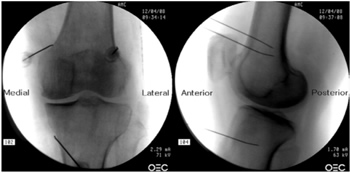

Radiofrecuencia de los nervios geniculados guiados por fluoroscopia

Para realizar una RFTNG guiados por fluoroscopia necesitamos una visión anteroposterior (AP) y lateral de la rodilla (Figura 2). Primero ubicamos al paciente en posición supina con una almohada debajo de la fosa poplítea (para que esté más cómodo) (16). Después de realizar asepsia y antisepsia de la rodilla, procedemos a ubicar los NG (Tabla II). El NGSL se encuentra avanzando la aguja de RFT hacia la confluencia de la diáfisis femoral lateral con el cóndilo femoral lateral en una visión AP y en un punto medio del fémur en una visión lateral. El NGSM se localiza avanzando la aguja hacia la confluencia de la diáfisis femoral medial con el cóndilo femoral medial en una visión AP y en un punto medio del fémur en una visión lateral. Por último, el NGIM se localiza avanzando la aguja hacia la confluencia de la diáfisis tibial medial con el epicóndilo tibial en una visión AP y en un punto medio de la tibia en una visión lateral (16,17).

Fig. 2. Proyección AP y lateral donde se observan las dianas terapéuticas usando fluoroscopia. Imagen tomada del artículo de Choi y cols. (9). Reproducido con la autorización de Jin Woo Shin.

Tabla II. Localización de los nervios geniculados guiados por fluoroscopia

Es muy importante tener una buena visión AP y lateral. En la proyección AP, la articulación tibiofemoral debe tener una anchura similar a ambos lados de la rodilla con el interespacio abierto (9). En la proyección lateral, debe existir una correcta superposición de ambos cóndilos femorales para realizar un bloqueo satisfactorio de los NGSM y NGSL (18).